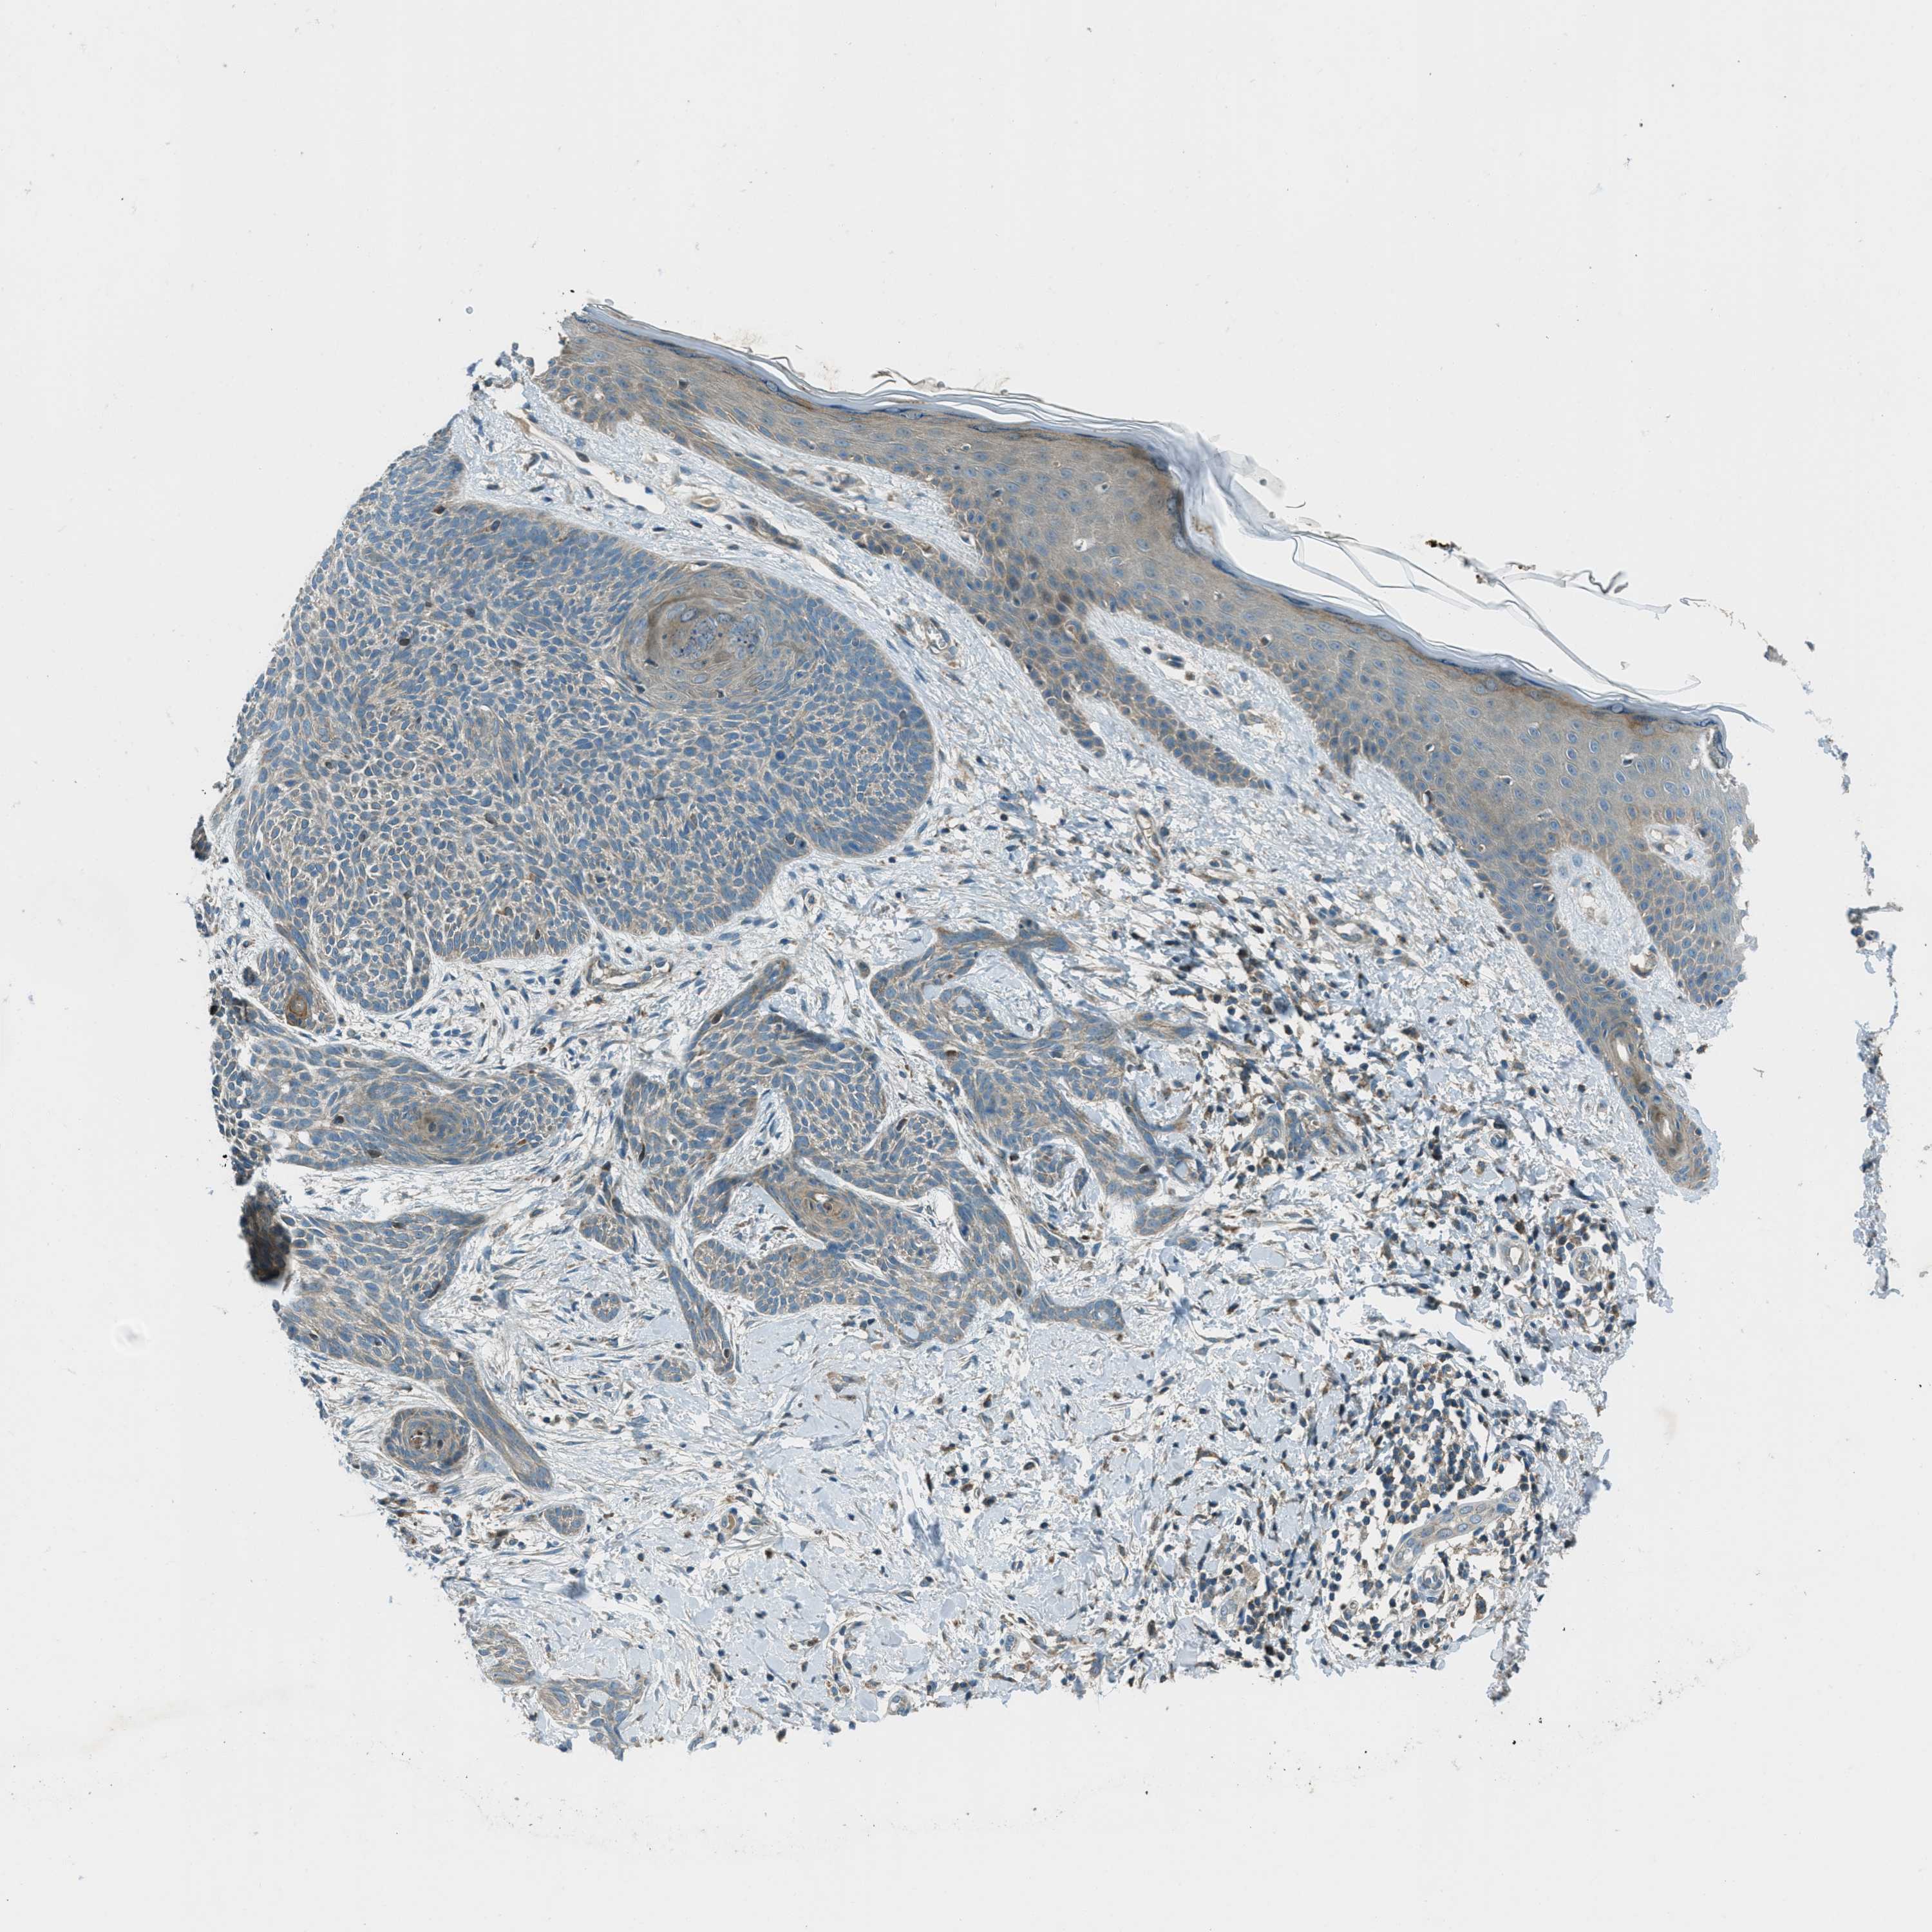

SKIN CANCER - Protein expressioni

A mouse-over function shows sample information and annotation data. Click on an image to view it in a full screen mode. Samples can be filtered based on level of antibody staining by selecting one or several of the following categories: high, medium, low and not detected. The assay and annotation is described here.

Antibody stainingi

Antibody staining in the annotated cell types in the current human tissue is reported as not detected, low, medium, or high, based on conventional immunohistochemistry profiling in selected tissues. This score is based on the combination of the staining intensity and fraction of stained cells.

Each image is clickable and will lead to virtual microscopy that enables deeper exploration of all samples and also displays staining intensity scores, fraction scores and subcellular localization as well as patient and tissue information for each sample.

Antibody HPA017322

Staining

High

Medium

Low

Not detected

Intensity

Strong

Moderate

Weak

Negative

Quantity

>75%

75%-25%

<25%

None

Location

Nuclear

Cytoplasmic/membranous

Cytoplasmic/membranous,nuclear

Squamous cell carcinoma in situ, NOS

Squamous cell carcinoma, NOS

Squamous cell carcinoma, metastatic, NOS

Basal cell carcinoma